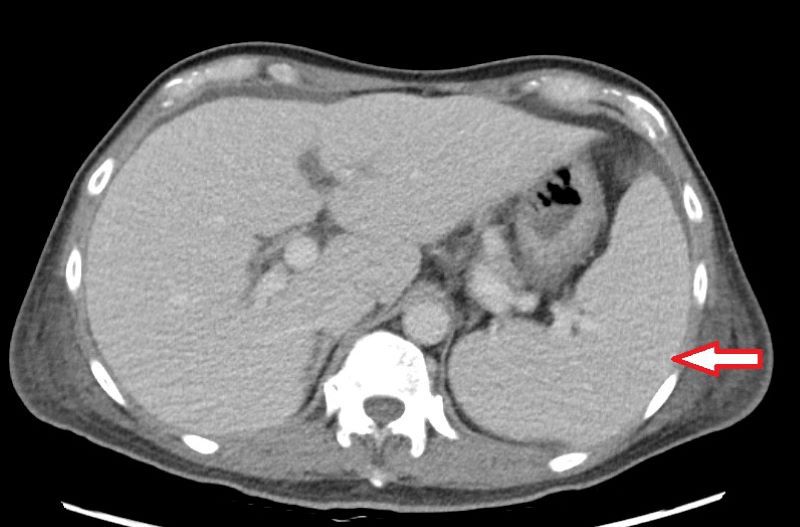

三尖瓣是位於心臟右心房與右心室之間的重要瓣膜,負責讓血液從右心房單向流入右心室,防止血液倒流,功能上與左心房和左心室之間的二尖瓣類似。楊凱文醫師指出,造成三尖瓣逆流的原因繁多,包括風濕性心臟病、感染性心內膜炎、二尖瓣或主動脈瓣疾病、心律不整,甚至是長期抽菸、慢性呼吸道疾病、自體免疫疾病均可能導致三尖瓣逆流。若三尖瓣功能受損,血液逆流回右心房,使右心房壓力增加,進而影響全身血液回流,就會導致器官壓力上升,當逆流非常嚴重且延遲治療,少部份病人甚至可能導致肝脾出現問題,如肝硬化、脾臟腫大等。而脾臟是造血器官,若因此腫大造成血球細胞破壞,就可能導致全身性血球減少,發生如林先生一般的情況。

三尖瓣逆流並不少見,國外統計指出,有高達70%-80%的健康人群可見輕微三尖瓣逆流;但中重度以上的三尖瓣逆流發生率則較低,約占整體人口的1%-2%。大多數患者初期多無明顯症狀,直至中重度以上才會有輕微水腫出現,因此許多人往往會忽略其嚴重性,待出現嚴重問題時多已經變成重度逆流。楊凱文醫師表示:「三尖瓣逆流大多可以用藥物控制,若是進展為重度逆流且藥物治療效果不彰,同時合併右心室功能異常,就會需要手術,但臨床案例不多。」診斷上,會以超音波檢查為主,手術則會視病人狀況選擇開胸或微創手術。以林先生為例,考量病人血球數值極低、免疫力差,擔心術中出血,醫療團隊以開胸手術替其更換人工瓣膜,並同步清除感染的贅生物。